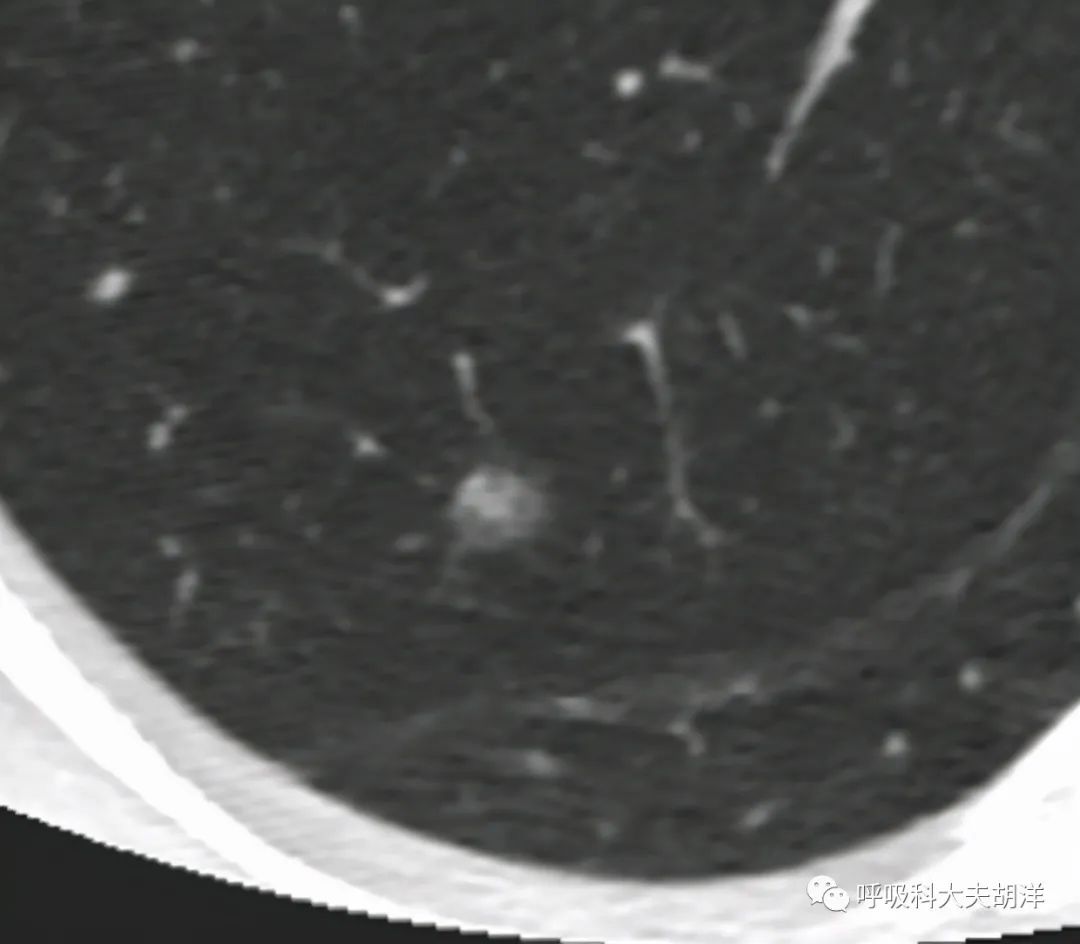

我们今天这个CT影像就比较清晰了,下图箭头所指的结节就是目标结节,注意看这个结节左半边比较淡,右上半边比较实,看起来就是一个混合性磨玻璃结节,这是恶性特征之一。

如果有这两个特征其实还可以随访,这个结节还有另外一个特征就是和周围组织分界不是很清楚,尤其是下图,是结节的放大照,可以看到密度较淡的部分和周围的分界尤其不明显,这是结节浸润性生长的一种表现,浸润的意思就像草纸上滴了一滴墨汁,墨汁会向周围扩散的意思,墨汁和干净草纸之间可能不会有明显的分界。

其实大家仔细看上图还能看到结节的另外一个特征,那就是毛刺影,这个结节周围有一些不仔细看看不到的细细的毛刺,有的短像从结节上发出的毫光,有的则是长长的毛刺像是太阳上甩出的太阳风暴,这些可能是长入结节的血管,下面这张放大图片就看的更加清楚了。